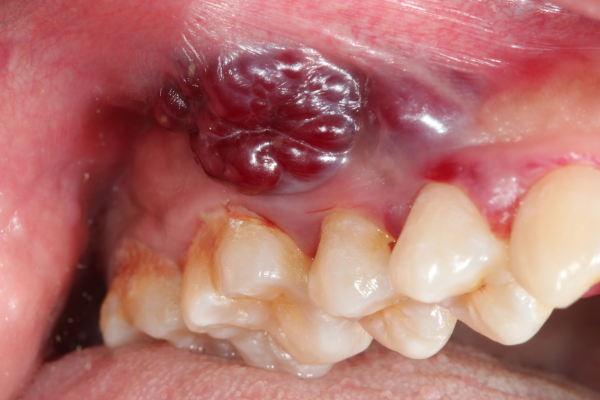

Verrucous Carcinoma – a variant of squamous cell carcinoma, verrucous carcinoma typically appears as a slow-progressing cauliflower-like growth.